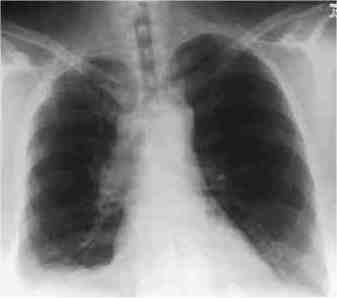

Small Cell Cancer Right Lung

On the left is a typical chest Xray appearance of a patient with small cell carcinoma of the right lung. The cancer is almost always central and often hidden by the heart and other central (mediastinal) structures, which can occasionally make it hard to see on a regular chest Xray.

It is often more obvious on a CT scan as the images below (from the same patient) demonstrate. Also on a CT Scan often only the malignant lymph nodes are visible and the area in the lung where the cancer actually started is not visible go here)